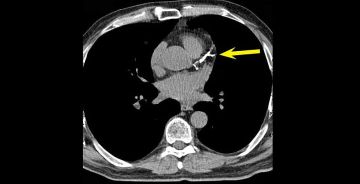

في توضيح طبي، أشار استشاري أمراض القلب الدكتور خالد النمر، إلى أن رقم تكلّس الشرايين (Calcium Score) غالبًا ما يرتفع تدريجيًّا مع التقدم في العمر، ووجود عوامل مثل ارتفاع ضغط الدم والسكري والتدخين، مؤكدًا أن الزيادة البسيطة لا تعني بالضرورة تدهور الحالة الصحية.

وضرب 'النمر' مثالًا بأن من كان لديه رقم تكلّس 30 وأصبح 52 بعد 4 سنوات، فإن هذه الزيادة تُعد طبيعية ومتوقعة، إذ إن المعدل السنوي المقبول عادة لا يتجاوز 20 إلى 25٪.

وشدد على أهمية السيطرة على العوامل المسببة مثل الضغط، والكوليسترول، والتدخين، والوزن، حتى لا تتسارع نسبة التكلّس وتؤثر على صحة الشرايين.